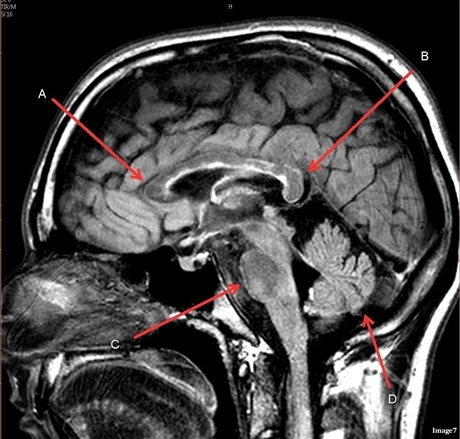

Image weighting and axis

T2 Flair

Sagittal

A

Genu Corpus Callosum

B

Splenium Corpus Callosum

C

Pons

D

Cerebellum